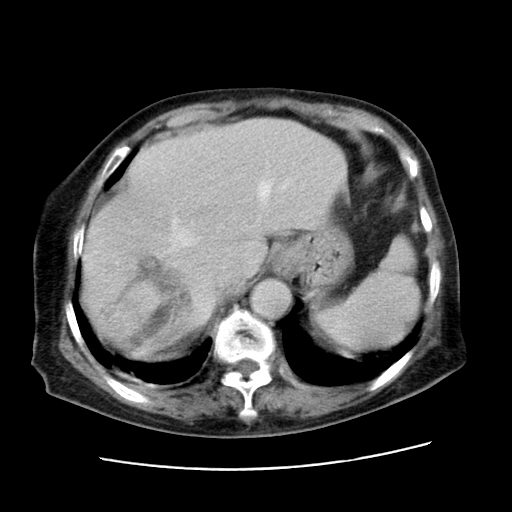

女,77.无不适

肝内胆管扩张,胆囊炎,胆囊窝积液。 右侧胸腔少量积液。

肝脏变异

肝右叶肝内胆管结石并肝内胆管扩张

胆总管扩张

肝右叶肝内胆管结石并肝内胆管扩张。另:慢性胆囊炎!胆囊窝积液!

肝右叶肝内胆管结石并肝内胆管扩张。胆总管下段梗阻,考虑壶腹部占位。

右侧肝内胆管局限性扩张,其内密度不均匀,扩张的胆管壁增厚,考虑肝内胆管炎合并结石可能性大